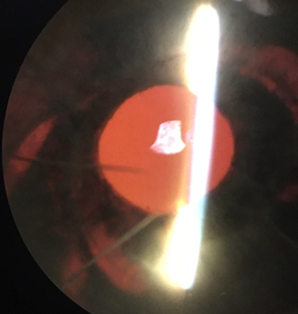

By day 13, 3+ cell remained (including RBCs) OD but flare decreased to a grade of 1+, allowing visualization of the iris and appreciable midperipheral circumferential transillumination defects (TIDs) at 1:00-4:00, 6:00-7:00, and 9:00-10:00, and no neovascularization of the iris (Figure 2). The PCIOL was present but flush with the iris. Gonioscopy revealed angles open to ciliary body 360 degrees OU with 1+ pigment in the trabecular meshwork OU, flat iris approach OU, and no evidence of neovascularization of the angle, angle recession, or peripheral anterior synechiae OU. The view to the retina OD remained hazy, but no appreciable vitritis or vitreous hemorrhage was noted. All anterior segment findings OS were within normal limits.

![]() Figure 2. Retro-illumination of the iris of the right eye on day 13: Circumferential transillumination defects 1-4:00, 6-7:00, and 9-10:00 are appreciable. They follow the shape of the IOL optic and haptics. Click to enlarge |

In this case and many others, TIDs can provide helpful clues in diagnosis of UGH syndrome. TIDs after cataract extraction are common, but pattern and location can differ based on cause. In contrast with pupillary margin TIDs caused by surgical instruments during cataract extraction, circumferential shape and mid-peripheral location of TIDs indicate chafing of the IOL optics and haptic on the posterior iris. This unique pattern is indicative of excessive PCIOL interaction with the iris and is frequently seen in UGH syndrome.5